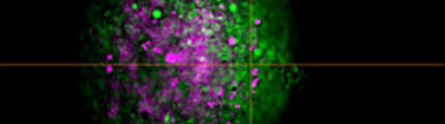

A new optical technique to help scientists observe live cells in 4D and understand what triggers them to mutate and spread disease around the human body is being led by the University of Nottingham.

The three-year project will result in a bespoke instrument, combining four cutting-edge optical microscopy technologies in a way that was not possible previously, in a single multifunctional platform.

The tool will image live cells in 4D, and, for the first time, plot, track and analyse the cells’ position, movement and function within the proteins and sugars that make up their environment (the extracellular matrix).

This will enable scientists to understand how physical and biochemical cues from cells influence the matrix, and vice versa, and how these interactions affect disease progression.